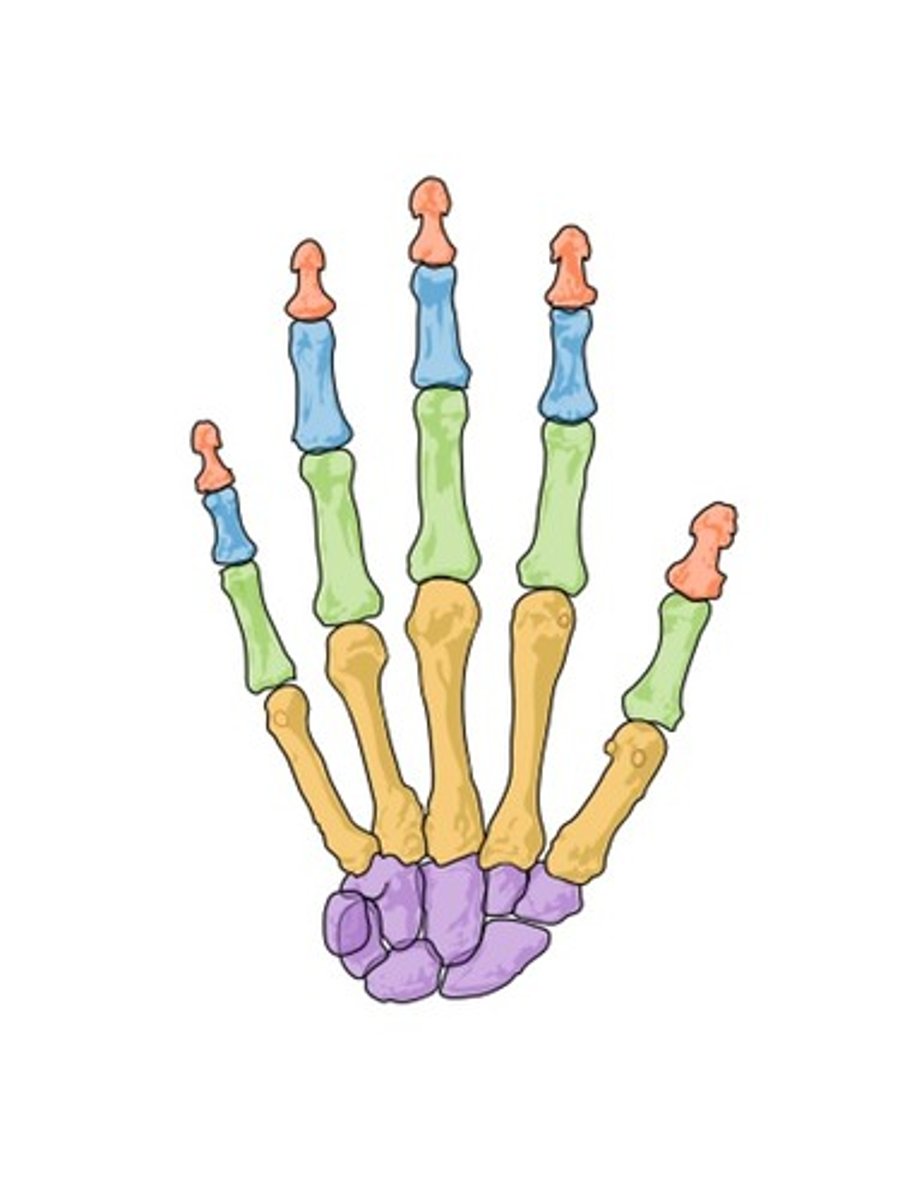

proximal phalanges

ID GREEN bones

middle phalanges

ID BLUE bones

distal phalanges

ID red bones

metacarpal

ID YELLOW bones

carpals

ID PURPLE bones